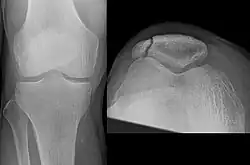

Osteochondral fracture of patella -

Vertical patella fracture